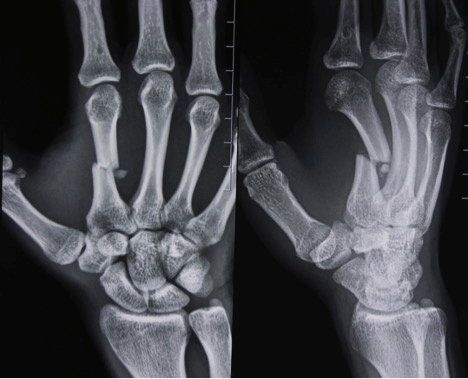

При подозрении на перелом кисти необходимо обратиться к травматологу. Первоначальный диагноз врач ставит на основе сбора анамнеза, анализа жалоб пациента и внешнего осмотра. Чтобы исключить вывихи или сильный ушиб, назначают рентген в двух или трех проекциях.

Клиническая картина при переломе ладьевидной кости: в большинстве случаев при осмотре выявляется отечность в области анатомической табакерки, движения в тыльно-лучевом направлении ограничены болью, пациент обычно не может сжать кисть в кулак. Диагностика перелома ладьевидной кости включает рентгенологическое обследование в трёх проекциях (прямой, боковой и косой), в некоторых случаях выполняется РКТ и МРТ.

Диагностика переломов

Большинство переломов дистального отдела лучевой диагностируются обычной рентгенографией в 2-х проекциях. Компьютерная томография (КТ) необходима при внутрисуставных переломах.

Для подтверждения диагноза выполняются рентгенограммы лучезапястного сустава в 2-х проекциях. Рентген являются наиболее распространенным и широко доступным диагностическим методом визуализации костей.